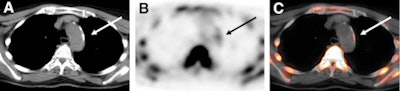

![]() |

| Transaxial F-18 NaF images from a 76-year-old woman include CT (A), PET (B), and fused PET/CT (C) images of the aortic arch. F-18 NaF uptake in atherosclerotic lesion coincided with calcification, as indicated by the arrows. Images courtesy of the Journal of Nuclear Medicine. |

For the remaining 223 lesions with F-18 NaF uptake (88%), researchers found radiotracer accumulation and calcification. However, the study stated, "only these 223 (12%) of the 1,930 total calcification sites showed prominent 18F-sodium fluoride uptake in at least some part of the calcified plaque."